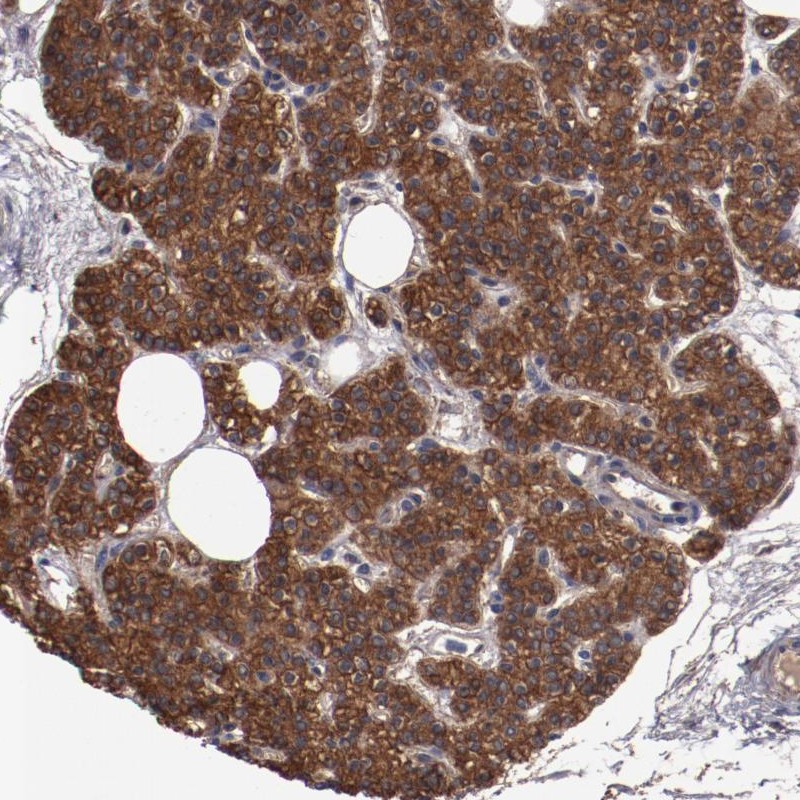

Immunohistochemical staining of human parathyroid gland shows strong cytoplasmic and membranous positivity in glandular cells.